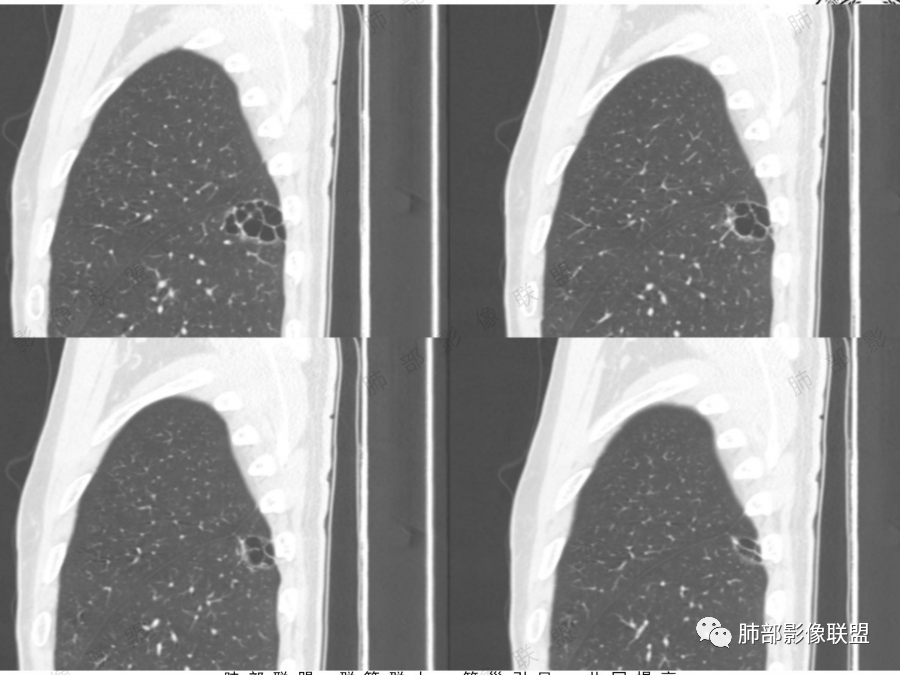

男51,体检发现肺部阴影,左肺下叶见多发薄壁囊腔影,可见结节,囊腔内见分隔,轻度胸膜牵拉,病灶周围少许磨玻璃影,常规考虑囊腔型腺癌,肿瘤标志物不高,除外结核。

中年男性,体检发现,吸烟史,但肺气肿背景不明显。左肺下叶囊腔病变,有一定张力,分隔明显,似有多个囊腔融合感,部分边缘见少许磨玻璃影,有支气管截断,首选囊腔型肺癌,某些先天病变(囊腺瘤样畸形等)也要考虑。

孤立性的多囊型病变伴分隔。ccam,肺隔离征,囊性肺癌,闭锁。。这是大家上面写的。看看怎么排除。血管看到肺动脉进入供血,没有感染液平,肺隔离不符合。没有代偿肺气肿,支气管没有闭锁,闭锁不考虑。那锁定ccam和肺癌。我们临床也常见是支气管畸形所致的囊。

我们看哪些内容,第1.周围有没有毛玻璃2.分隔有无粗细不均或结节,壁有无厚薄不均有无壁结节3.支气管,4.随访。

男性,体检发现左肺阴影。影像表现:左上肺多发结节伴纤维条索影,部分钙化,左下肺囊腔样改变,内有分隔,部分分隔边缘见实性成分及GGO样改变,支气管从旁边经过,或受压,无明确进入依据。初步诊断:1、左上肺结核。2、左下肺囊腔型腺癌,诊断依据:分隔样囊腔,部分分隔有实变,边缘有GGO改变,鉴别诊断:1、囊腺瘤样畸形,分隔样囊腔要考虑,但部分分隔实变,部分伴GGO样改变成疑,最大的疑问是年龄51岁,体检发现,抽烟、饮酒30年,却无发病,可能性太小。2、囊腔性转移,单发分隔样囊腔转移少见,且需要病史支持。3、囊性淋巴瘤,一般以单发囊腔多见,分隔样囊腔型淋巴瘤罕见。4、感染,无相关临床症状及辅检支持,基本排除。

@傅昌瑜—贺州市人民医院—呼内 里面的血管进一步支持恶性。但不鉴别腺癌和鳞癌,主要鉴别的,还是多囊,张力较高,囊壁较薄(实变区除外),加GGO。